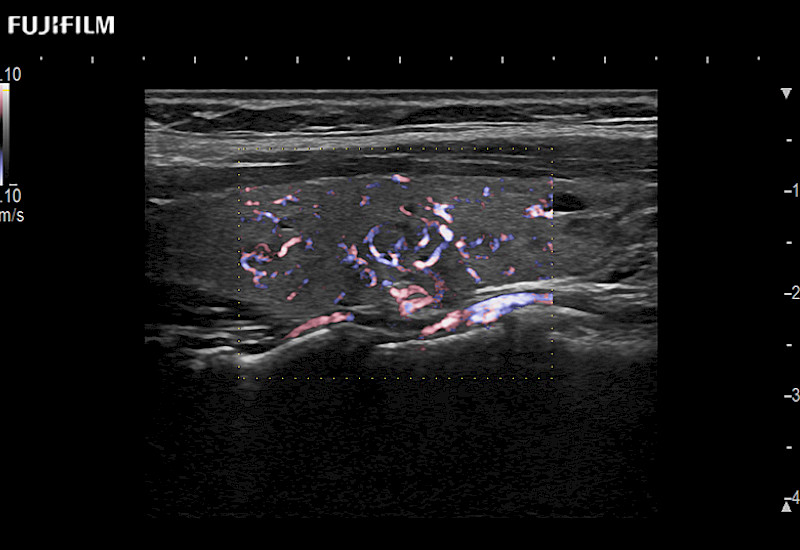

Extraordinary high-resolution digital imaging

Multi-Parametric imaging modalities

- Instant feedback on tumor margin delineation

- Valuable information to guide tumor resections